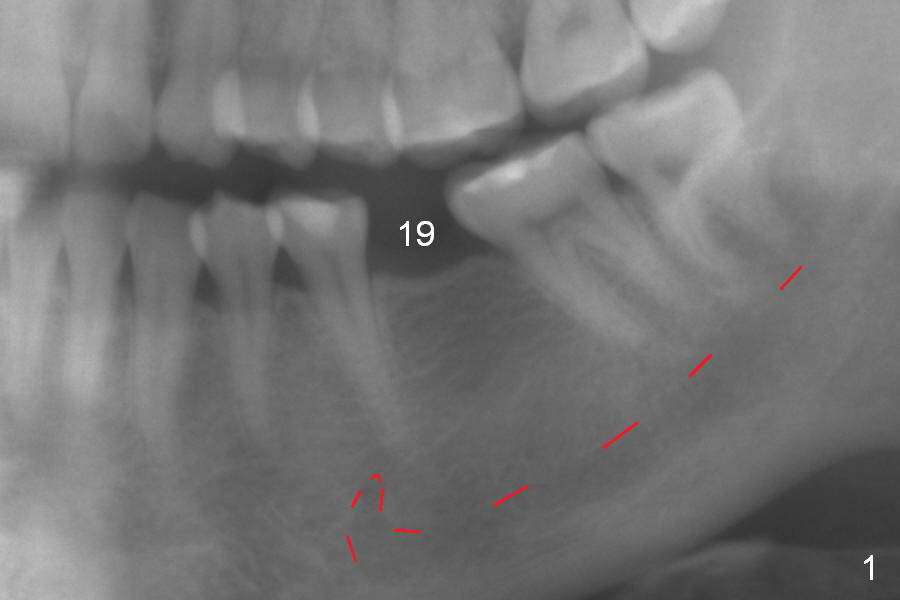

In fact, the buccolingual width of the ridge is sufficient to have a 4.5x11.5 mm implant placed (Fig.4,5, D3 bone, <35 Ncm). Proximal reduction is done before and after placement of a 5.5x4(3) mm abutment. Heavy abutment height adjustment is provided as well as the opposing prior to immediate provisional.

There is no bone loss 3 months postop (Fig.6).